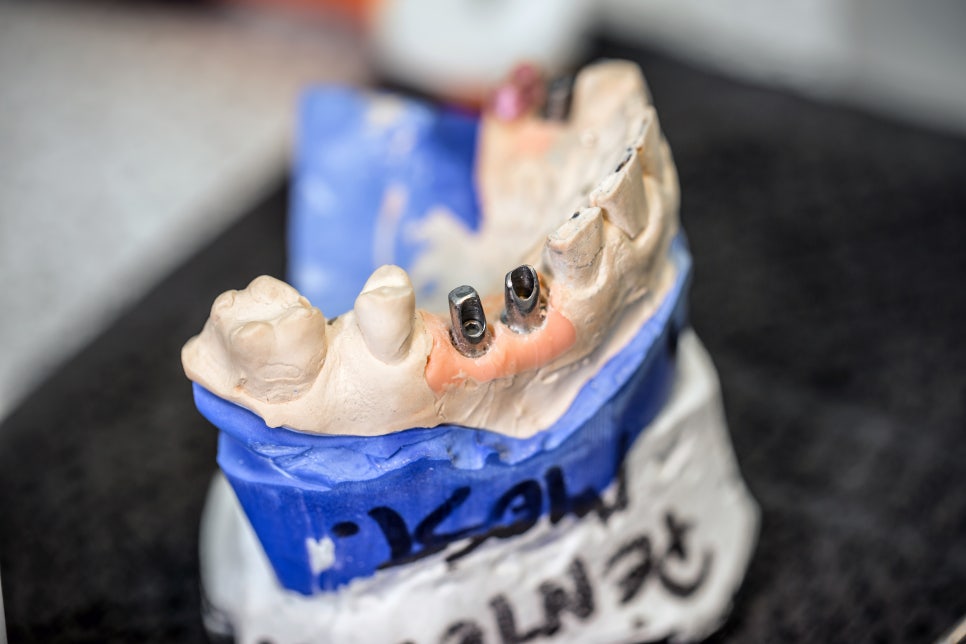

논현동임플란트잘하는곳 저희 뉴엔은

임플란트 수술 시 3D 구강스캔 및

CT, 컴퓨터 모의 수술 과정과 수술

가이드를 이용하여 출혈이 적고

명확하고 빠른 치료가 가능하도록

시행하고 있습니다.